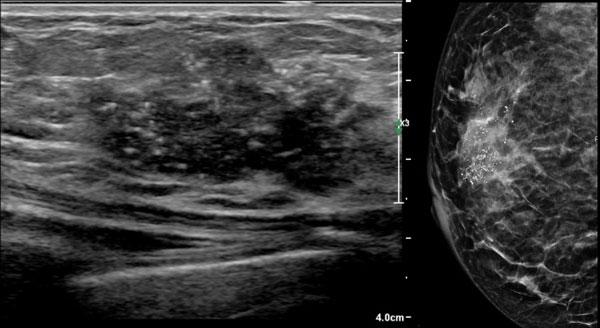

Đây là hình ảnh của một phụ nữ 50 tuổi tự sờ thấy khối u ở vú.

Hãy mô tả các dấu hiệu siêu âm, sau đó tiếp tục đọc.

Các dấu hiệu siêu âm bao gồm:

- Khối giảm âm với hình dạng không đều

- Bờ không rõ ràng, vừa có góc cạnh vừa mờ nhạt

- Các chấm tăng âm nhỏ, tương ứng với các vôi hóa

- Không có bóng cản phía sau hoặc tăng âm phía sau

Các vôi hóa này cũng được quan sát thấy trên hình ảnh nhũ ảnh.

Vùng trắng trên nhũ ảnh chính là khối u.